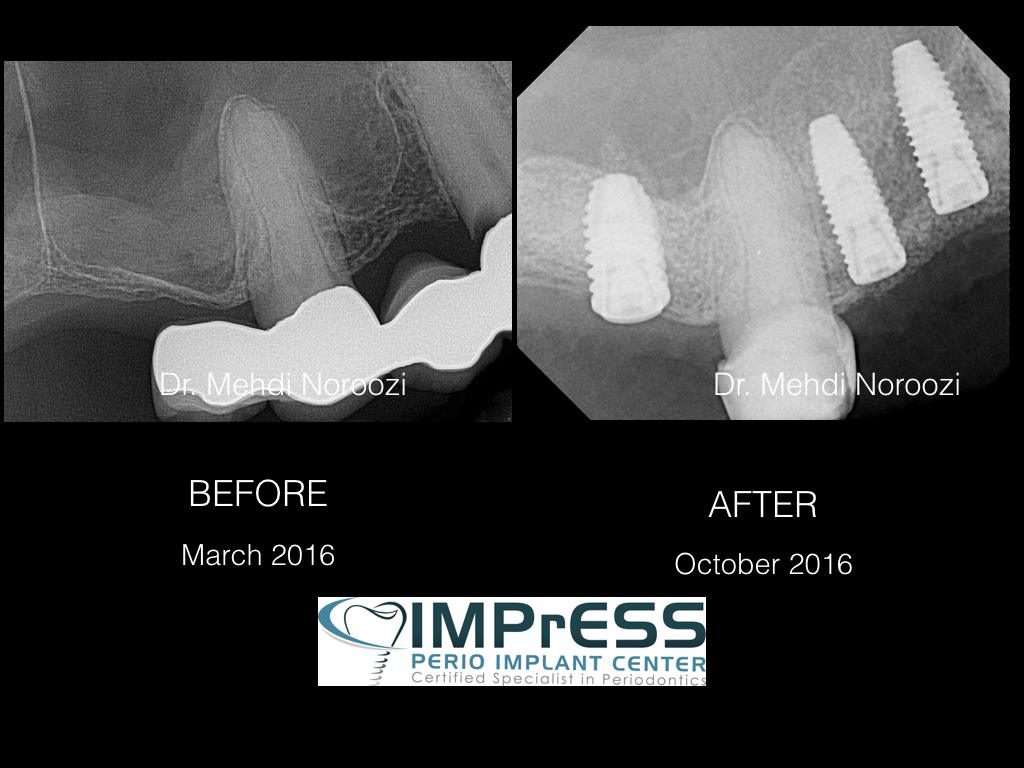

Our Specialists in IMPrESS Perio Implant Center have undergone extensive training in sinus lift surgery and have developed tremendous experience and skills over years to safely perform the sinus lift surgery with predictable treatment outcome.

Dr. Noroozi utilizes the most advanced technologies such as Piezosurgery to make your sinus lift surgery safer, more effective and comfortable for you.

The bone used in a sinus lift may come from your own body (autogenous bone), from a cadaver (allogeneic bone) or from cow bone (xenograft). You will need X-rays taken before your sinus lift so the dentist can study the anatomy of your jaw and sinus. You also may need a special type of computed tomography (CBCT) scan. This scan will allow the dentist to accurately measure the height and width of your existing bone and to evaluate the health of your sinus.

After a sinus lift, you need to wait several months for the bony material to harden and integrate with your jaw. Depending on the grafting material used, implants may be placed in four to nine months.